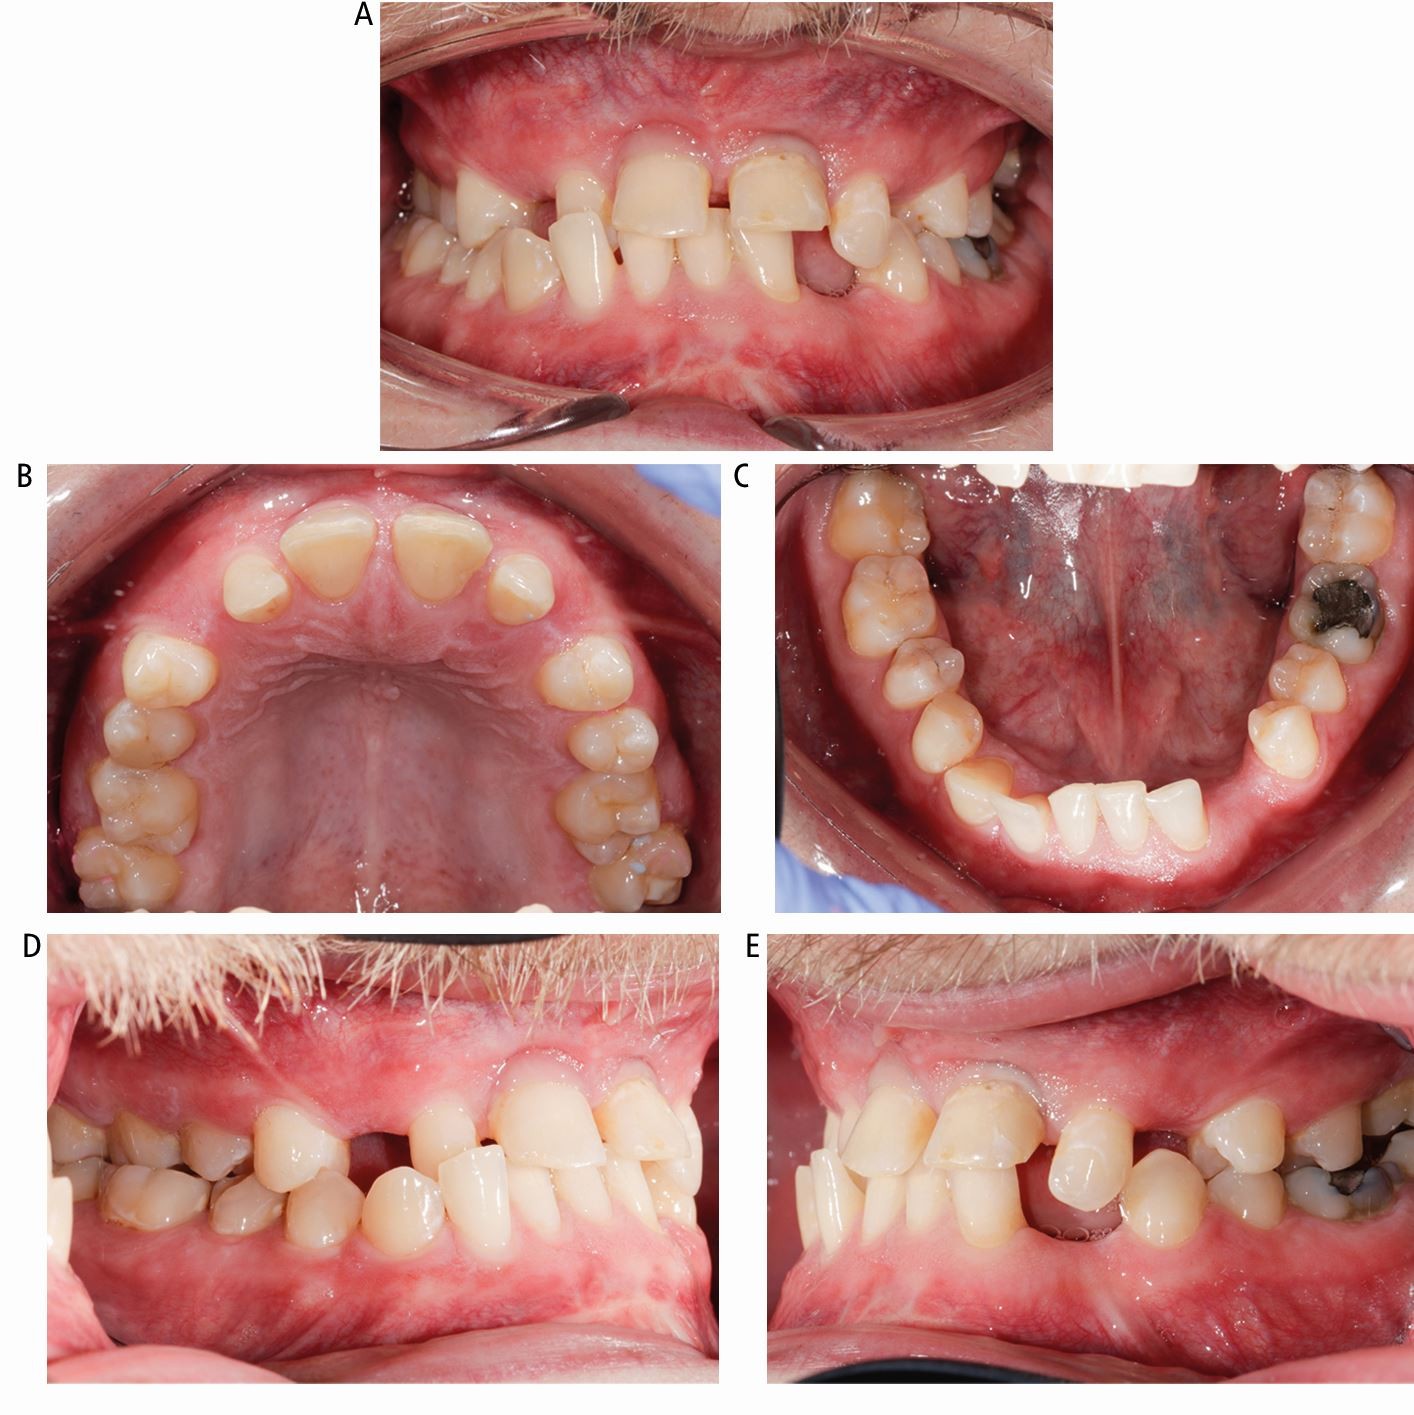

Fig. 2

From: Craniofacial fibrous dysplasia: a challenge for general dental practitioners

Case 1: intra-oral appearance of the teeth. (A) Cross bite and deep overbite and missing teeth. (B) Expansion of the anterior maxilla with spacing. (C) Expansion of the anterior mandible with spacing and crowding. (D, E) Right and left buccal views